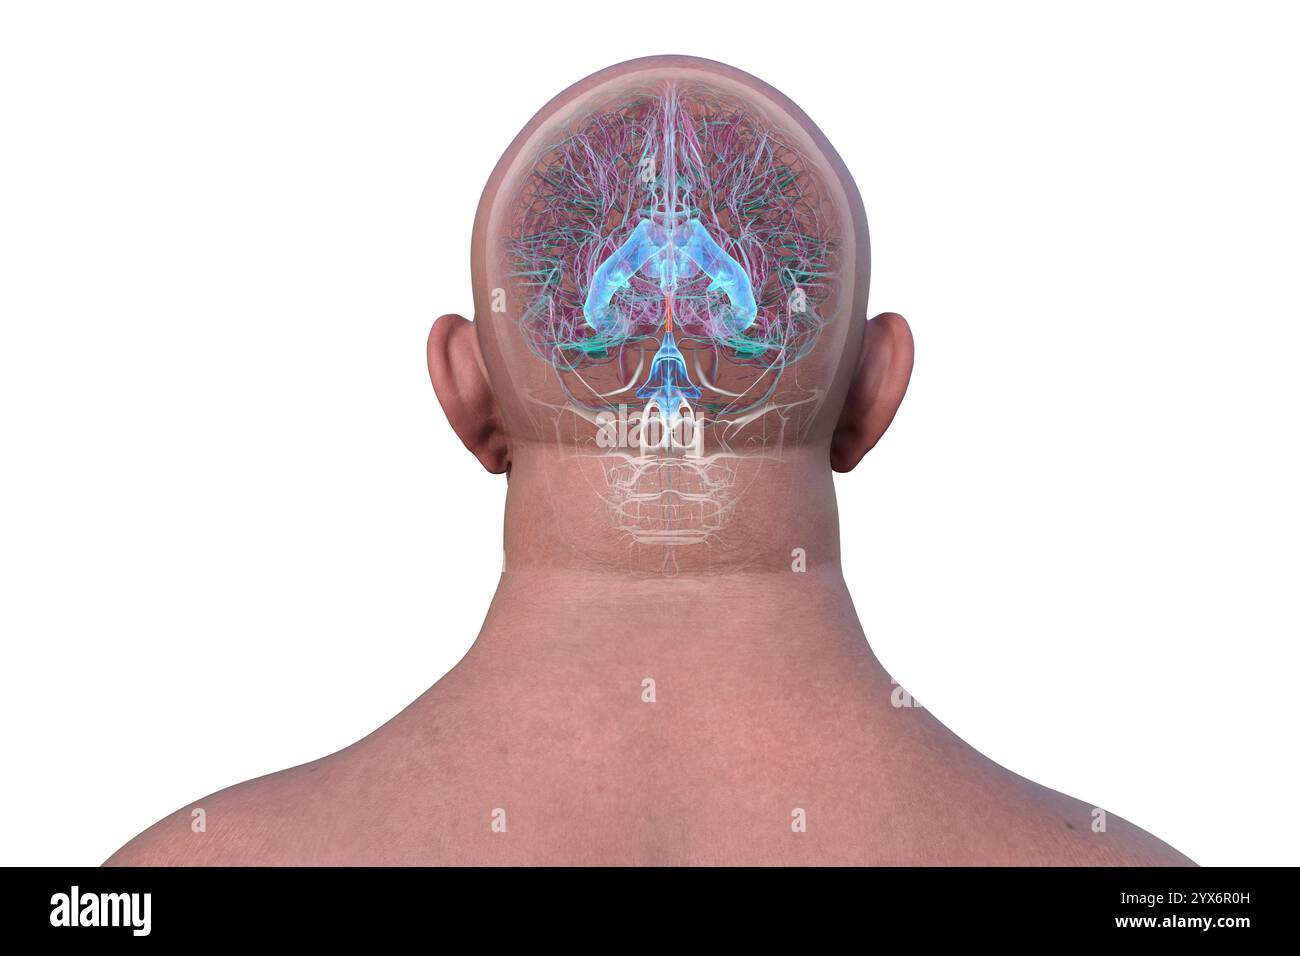

RF2YX6R0H–Computerdarstellung des menschlichen Gehirns mit orangefarbenem Aquädukt und grünem Ventrikelsystem, die den Liquorfluss (CSF) zeigen. Rückansicht.

RF2YYB740–Computerdarstellung des menschlichen Gehirns mit orangefarbenem Aquädukt und grünem Ventrikelsystem mit Liquorfluss. Rückansicht.

RF2YYB755–Computerdarstellung des cerebralen Aquädukts (orange), eines schmalen Kanals im Mittelhirn, der den dritten und vierten Ventrikel verbindet und den Liquorfluss erleichtert. Rückansicht.

RM2CE564C–. Erkrankungen des Nervensystems . Abb. 43. – Basis der Braix axd Hirnnerven. Sucht nach ihren Hauptabteilungen im Menschen, der Korpora quadrigemina (siehe Abb. 44und 45) oben die Spalte von Sylvius unten, und darunter die Fasermasse der oberen Pedunkles des Kleinhirns und der Pedunculi cerebri (Abb. 46, 47, 48, 49). Seine Kerne (Neuronenzellen) liegen entlang der gesamten Länge des Aquädukts von Sylvius, von seinem frontalen Ursprung fast bis zu seinem kaudalen Ende;5 52 HISTOLOGIE DES ZENTRALNERVENSYSTEMS die Kerne der trochlearen Nerven liegen posteriorly dort, wo der aque-Ductus liegt

RF2YYB752–Computerdarstellung des cerebralen Aquädukts (orange), eines schmalen Kanals im Mittelhirn, der den dritten und vierten Ventrikel verbindet und den Liquorfluss erleichtert. Rückansicht.